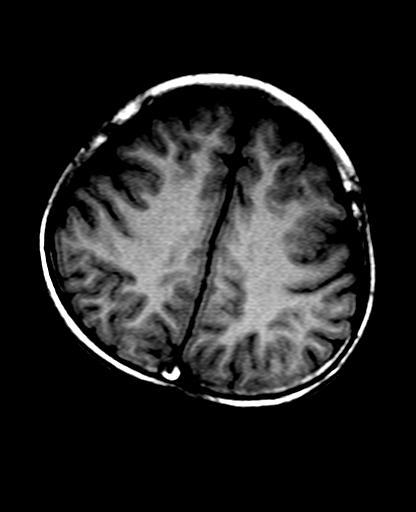

标题: PED2848:脑内病变2

头痛10天、间断呕吐2天。f 6岁

入科化验血清铜及铜兰蛋白均减低,脑脊液正常,血清神经原烯醇化酶明显增高。wbc:5.94x109/l、

临床表现及实验室检查符合肝豆状核变性

mri未见明显异常。但临床支持考虑肝豆状核变性。